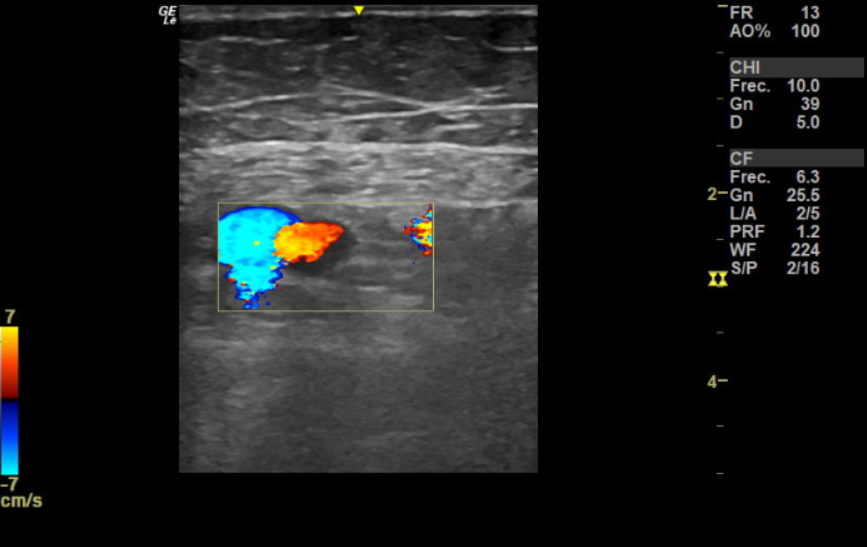

Se realiza ecografía de compresión a pie de cama, negativa en femoral derecha. Femoral izquierda no compresible por completo y con relleno incompleto de flujo Doppler, sin clara imagen de trombo en su interior.

El diagnóstico principal, basado en la sospecha clínica y prueba de imagen, fue de trombosis venosa profunda (TVP) femoral izquierda.

La ecografía fue clave para la identificación de la TVP femoral, lo que permitió la elección de un tratamiento dirigido. Este caso resalta la necesidad de considerar la TVP como diagnóstico diferencial en pacientes de edad avanzada con síncope, especialmente en presencia de factores de riesgo como inmovilidad o signos clínicos de trombosis. La colaboración entre atención primaria y urgencias es esencial para la detección y manejo adecuados de esta patología.